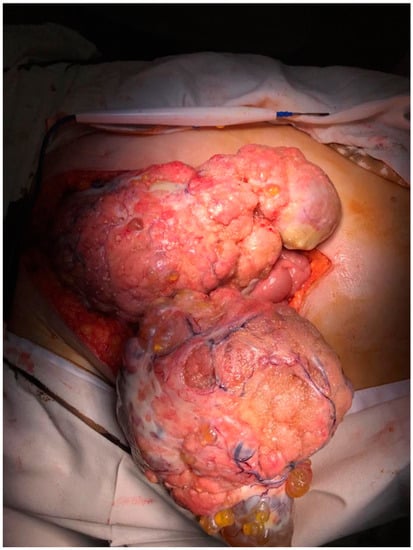

2. Case Presentation